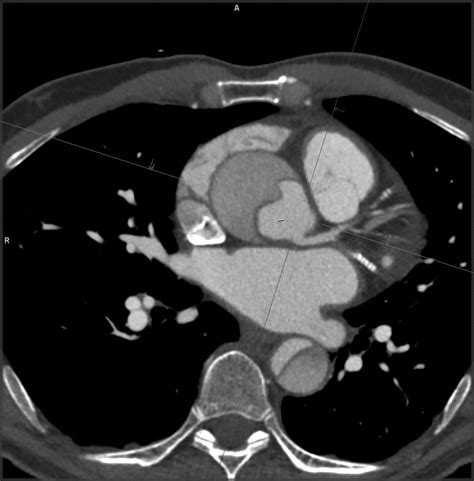

• Reconstruction: The raw data is processed into 3D images, allowing surgeons to visualize the exact anatomy of the flap and its relation to critical branch vessels.

The primary goal of the Aortic Dissection CT is to identify the "intimal flap"—the physical separation of the aortic layers. Radiologists categorize these findings based on the Stanford or DeBakey systems, which help surgeons decide the urgency of the repair. The report will typically detail several critical features:

Advanced post-processing techniques now allow surgeons to view the dissection in high-fidelity 3D models. This technological leap enables the surgical team to map out the placement of stents or grafts with millimeter precision before even entering the operating room. Such preparation reduces the time spent under anesthesia and improves the overall prognosis for the patient, marking a significant advancement in vascular medicine.